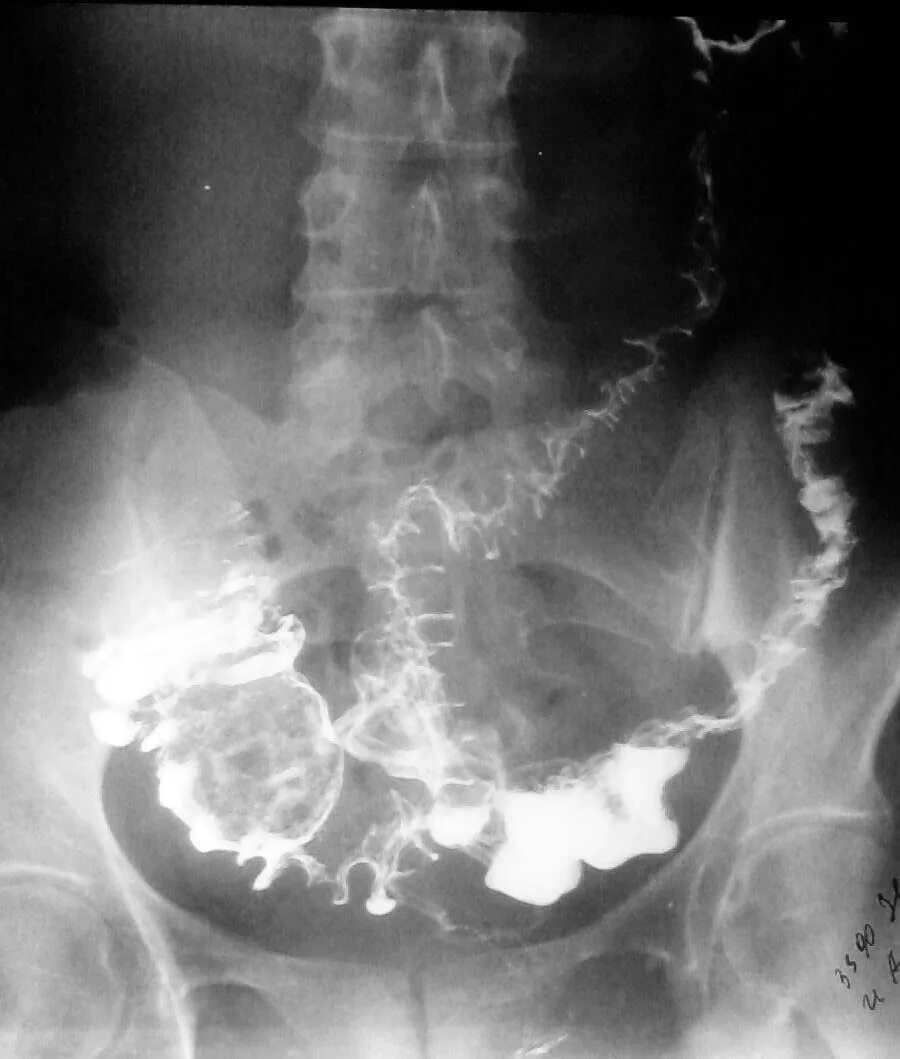

Кишечник после ирригоскопии